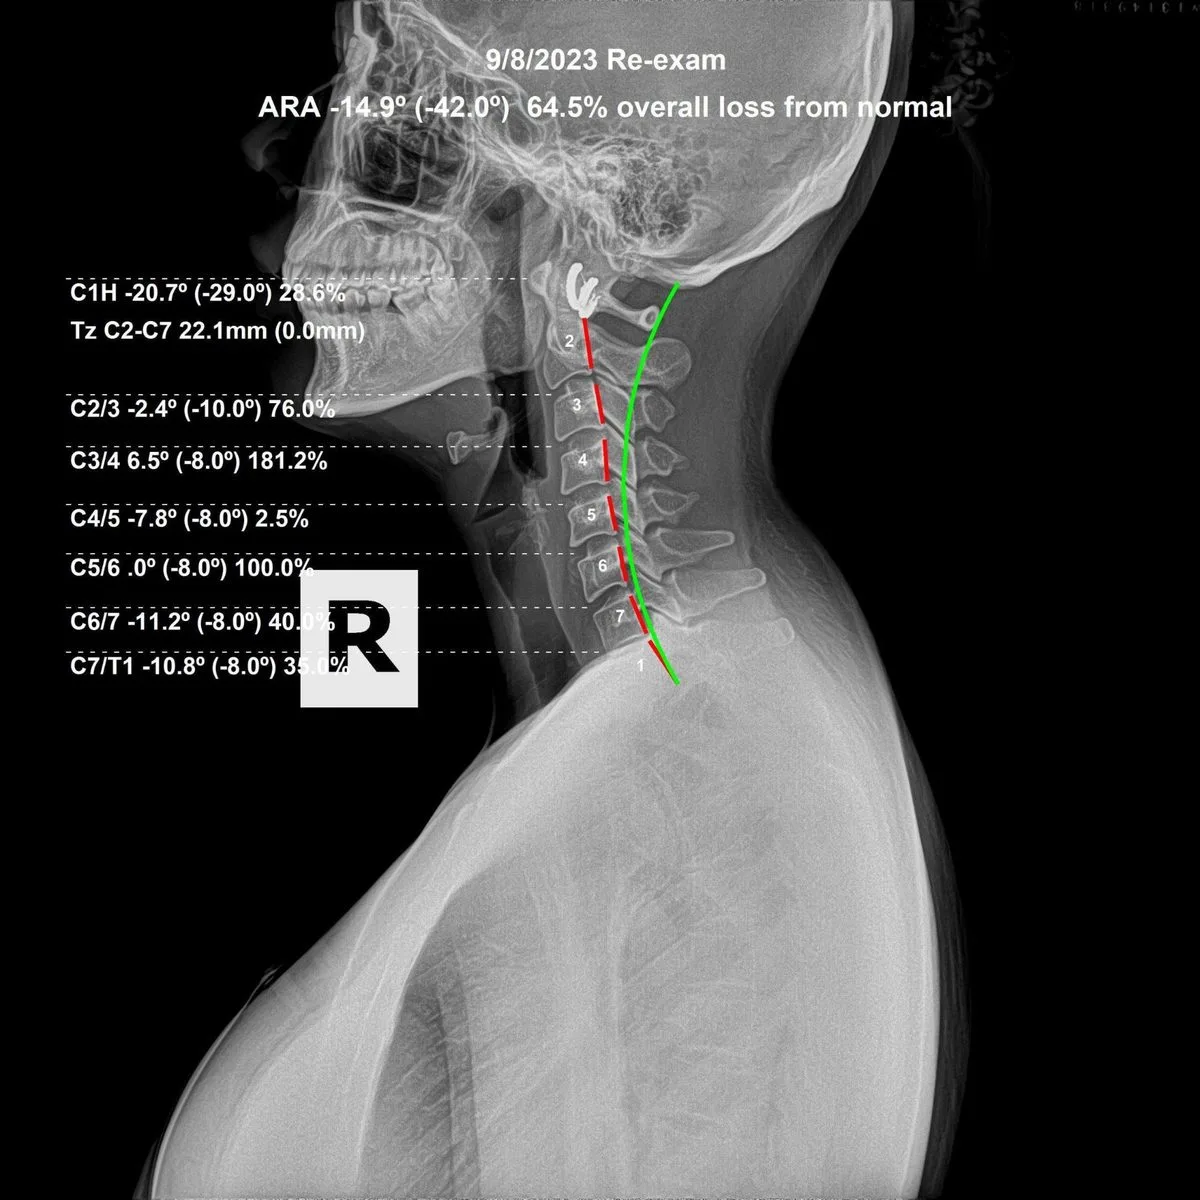

Cervical spine X-ray — subluxation analysis at Rochet Family Chiropractic Royal Palm Beach FL

Your first visit begins with a consultation — a conversation, not a sales pitch. Dr. Rochet will review your health history and listen to what brought you in. From there, spinal X-rays are taken to establish your baseline and identify where vertebral subluxations are present, how long they have been there, and what the structural picture looks like.

On your second visit, Dr. Rochet reviews your X-rays with you in detail. You will see exactly what your spine looks like and where the interference is. A specific care plan is then developed — not a generic program, but one built around your spine, your age, and your goals.